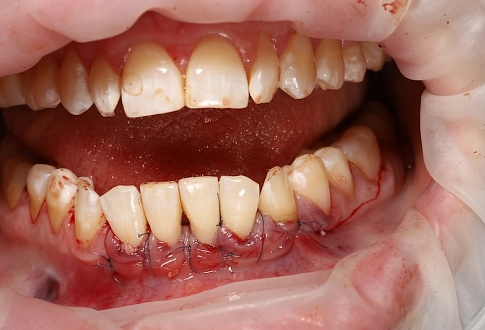

Наращивание десны

Фото «До» и «После»

Внимание! Изображение может вызвать шок или неприятные эмоции.